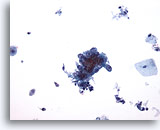

Figure 86

Bronchial wash

Tadpole shaped cells maybe seen in squamous cell carcinoma.

20x

Bronchial wash

Tadpole shaped cells maybe seen in squamous cell carcinoma.

20x